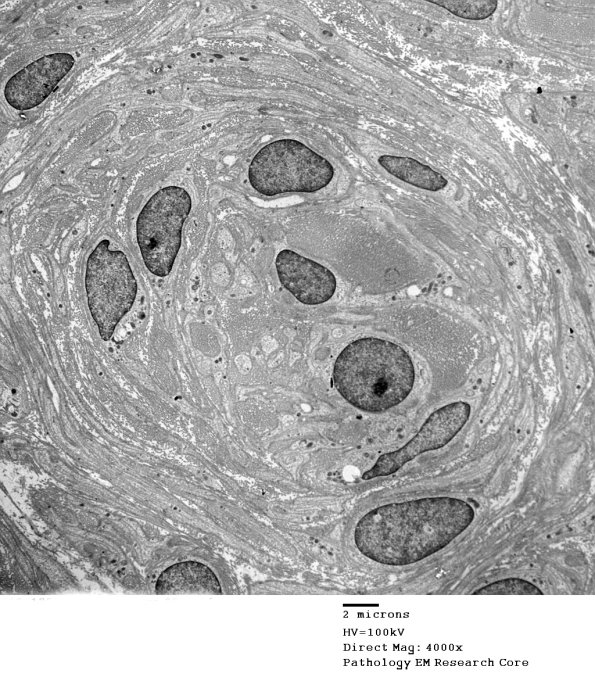

Washington University Experience | PERIPHERAL NEUROPATHY | 20 PSEUDO-ONION BULBS | 2F14 (Case 2) Nerve_058 - Copy

Additional examples of the gamut of pathologies found in POB. (electron micrographs) ---- Classic OB with a central demyelinated axon surrounded by imbricated Schwann cell processes were rare, perhaps nonexistent, in this case.